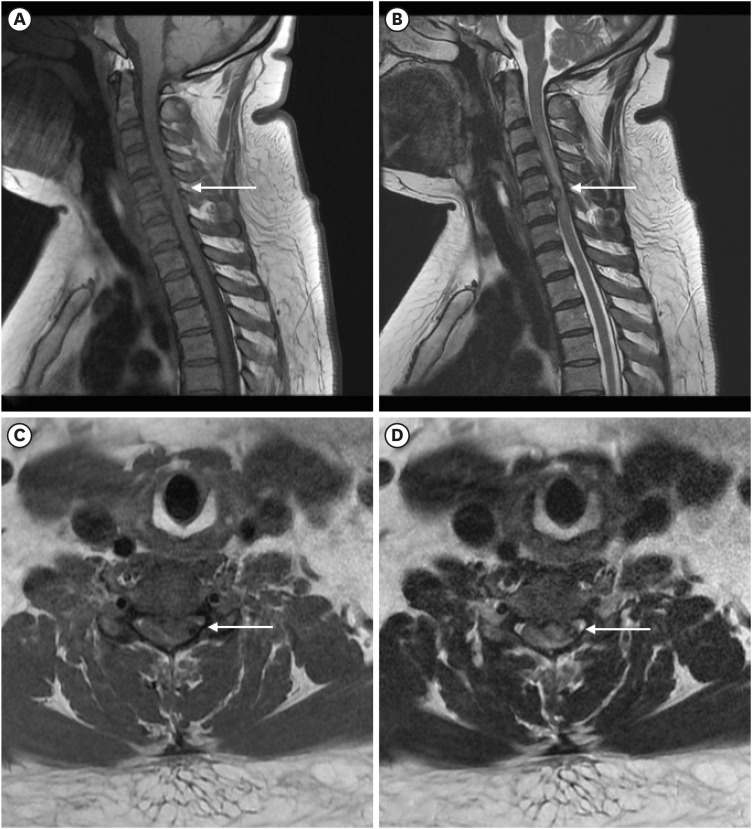

Intradiscal electrothermal therapy (IDET) is a minimally invasive procedure that alleviates chronic discogenic pain by delivering controlled heat to modify collagen and destroy pain-conducting nerve endings. While IDET offers a less invasive alternative to surgery, it carries risks such as nerve damage, infection, vertebral osteonecrosis, and, rarely, spinal cord injury. This report presents the case of a 36-year-old woman who developed left-sided hemiparesis following IDET for cervical disc herniation at the C5/6 level. Magnetic resonance imaging revealed cervical cord edema, and examination revealed neurological deficits, including reduced proprioception, motor strength, and senses of pain and temperature. Anterior cervical discectomy and fusion led to thermal injury on the left ventral spinal cord, and postoperative recovery resulted in significant neurological improvement, although some sensory deficits persisted. This case underscores the importance of appropriate patient selection and meticulous procedural technique to prevent severe complications, emphasizing the importance to reserve IDET for specific cases and to consider alternatives for more complex spinal conditions.